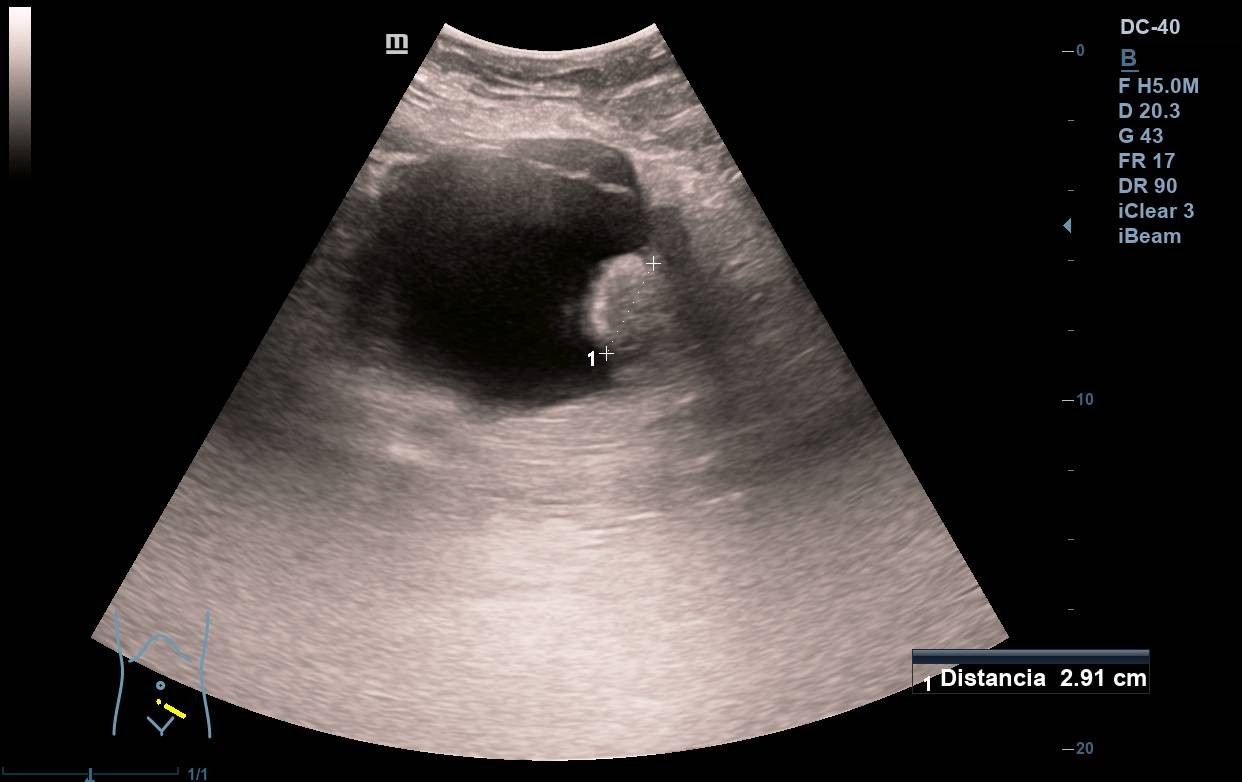

Paralelamente realizamos una nueva ecografía en Atención Primaria con intención formativa, objetivando entonces de manera inesperada que la vejiga, bien replecionada, no presenta lesiones en su interior. Por el contrario, al bascular el transductor se observa una tumoración dependiente de ovario izquierdo, que, sin valorar adecuadamente la proyección, podría parecer ser intravesical.

Adenocarcinoma de colon metastásico. Resección de metástasis de adenocarcinoma enteroide de 5 x 4 cm sobre cistoadenoma seroso en ovario izquierdo.